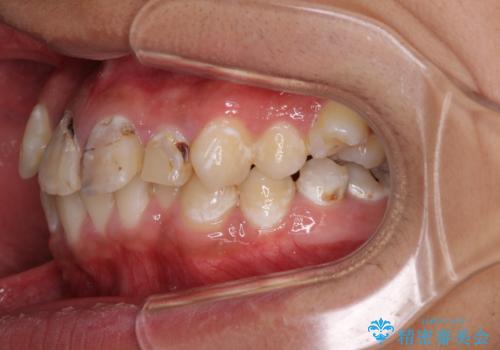

矯正治療は、むし歯が酷く抜歯が望ましい歯を1本抜歯して、ワイヤー装置にて整えることとしました。

矯正治療後は上顎前歯4本をオールセラミッククラウンにて補綴治療を行うこととしました。

むし歯が多かったため、ワイヤー矯正中に処置したむし歯が悪化することが懸念されましたが、歯磨きをしっかりと行ってくれたため、とても良好な状態を維持することができました。